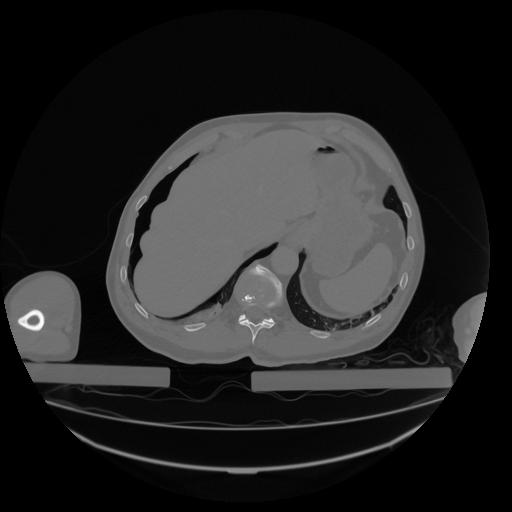

34 CUERPO,CE,Vol,1.0,CUERPO,,